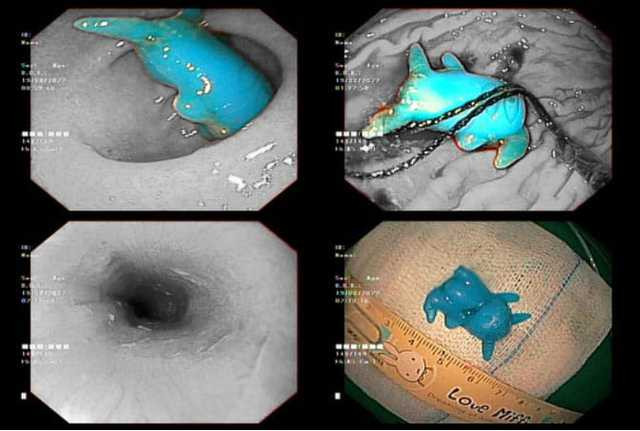

Bệnh viện Nhi đồng 2 TP.HCM vừa nội soi cấp cứu lấy dị vật là đồ chơi pikachu bằng nhựa, kích thước 2x2, 5x1cm, bị kẹt ở thực quản cho bệnh nhi 6 tuổi. Hình thù đồ chơi có sừng dài dễ đâm lủng thực quản và gây khó khăn trong quá trình xử trí.

Người nhà chia sẻ, trong lúc chơi pikachu bé cho vào miệng ngậm và không may nuốt vào. Bé than đau ngực, gia đình đưa đến bệnh viện địa phương, sau đó chuyển lên bệnh viện Nhi Đồng 2. Bé được chẩn đoán theo dõi dị vật kẹt thực quản. Sau khi nội soi cấp cứu, pikachu được lấy ra. Hiện sức khỏe của trẻ ổn định.

Dị vật là đồ chơi pikachu bằng nhựa, có kích thước 2x2, 5x1cm.